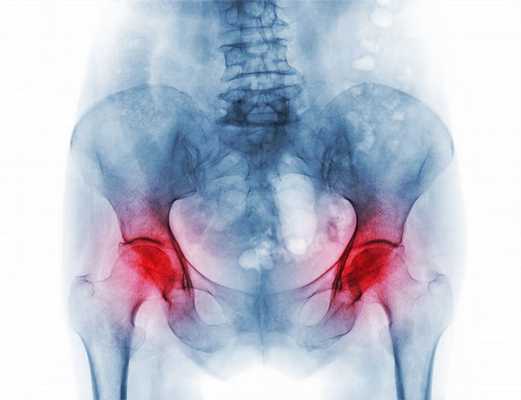

- Сенильный. Возникает у пожилых людей во время процессов старения костно-хрящевого каркаса и возрастных дегенераций. Сопровождается переломами при незначительных ушибах и падениях, слабостью мышц и костей. Самый распространённый вид — остеопороз шейки бедра, который в 30% случаев заканчивается летальным исходом.

Первичный постменопаузальный остеопороз — наиболее распространенный вариант остеопоретической болезни, составляющий более 85% в структуре этого метаболического заболевания костно-мышечной системы. По данным ВОЗ, денситометрически подтвержденное снижение минеральной плотности костей и нарушение их микроархитектоники наблюдается у 30-33% женщин старше 50 лет. В России частота типичных для остеопороза переломов предплечья составляет более 560 случаев на 100 тысяч пациенток постменопаузального возраста, остеопоретических переломов бедра — свыше 120 на 100 тыс. Социальная значимость патологии определяется ее влиянием на инвалидизацию и смертность пожилых женщин.

Практически у половины женщин заболевание протекает бессимптомно и выявляется только после перелома, вызванного незначительной травмой. В остальных случаях симптоматика прогрессирует постепенно. По мере потери костной массы пациентка начинает ощущать боли в пояснично-крестцовой области, усиливающиеся во время поднятия тяжелых предметов, поворотов, ходьбы. В последующем появляется ощущение тяжести в межлопаточном пространстве, болезненность в тазовом кольце, длинных трубчатых костях голени. Чтобы избавиться от болей и дискомфорта, на протяжении дня требуется дополнительный отдых в положении лежа.

Нарастание интенсивности болезненных ощущений приводит к тому, что со временем они беспокоят больную даже в состоянии покоя. Обычно нарушение осанки и искривление позвоночника сопровождается кифозом. Часто женщины постменопаузального возраста с остеопорозом жалуются на слабость, быструю утомляемость при физических нагрузках. Крайними формами проявления патологии становятся компрессионные переломы нижнегрудных и верхних поясничных позвонков с уменьшением их высоты, спонтанные или возникающие при незначительных нагрузках переломы лодыжек, костей предплечья, шейки бедра. Характерный признак — снижение роста на несколько сантиметров за год.